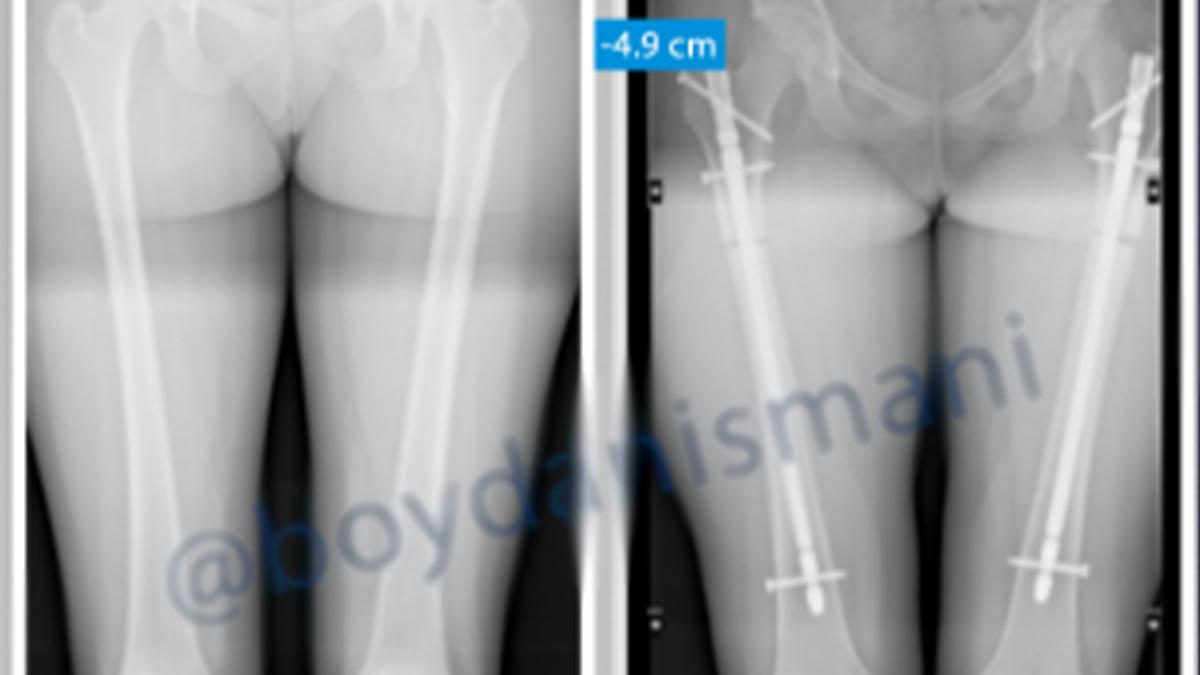

Boy kısaltma ameliyatında, uyluk kemiği kesilerek bir kısmı çıkarılıyor. Ardından kemik uçları metal bir çubukla sabitleniyor. İyileşme süreci tamamlandıktan sonra bu çubuk çıkarılıyor.

Operasyon sayesinde üst bacakta en fazla 5,5 cm, alt bacakta ise 3 cm’ye kadar kısalma yapılabiliyor.